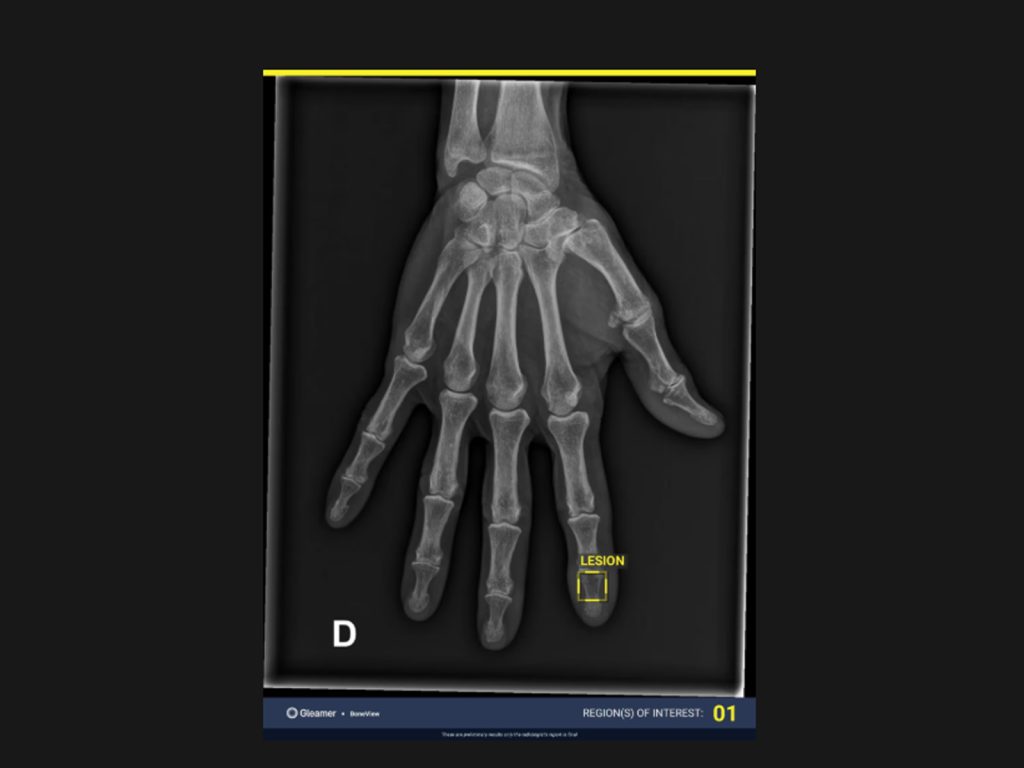

BoneView este o soluție de inteligență artificială care analizează radiografiile pentru a detecta automat fracturi și alte leziuni osoase. Aplicația examinează imaginile în câteva secunde și evidențiază zonele suspecte direct în PACS, ajutând medicii să identifice rapid patologia care poate fi omisă în citirea manuală.

Rezultatul este primit direct in viewer PACS si contine

• Contur „bounding-box” ce evidentiaza locatia patologiei detectate

• Numar al ariilor de interes